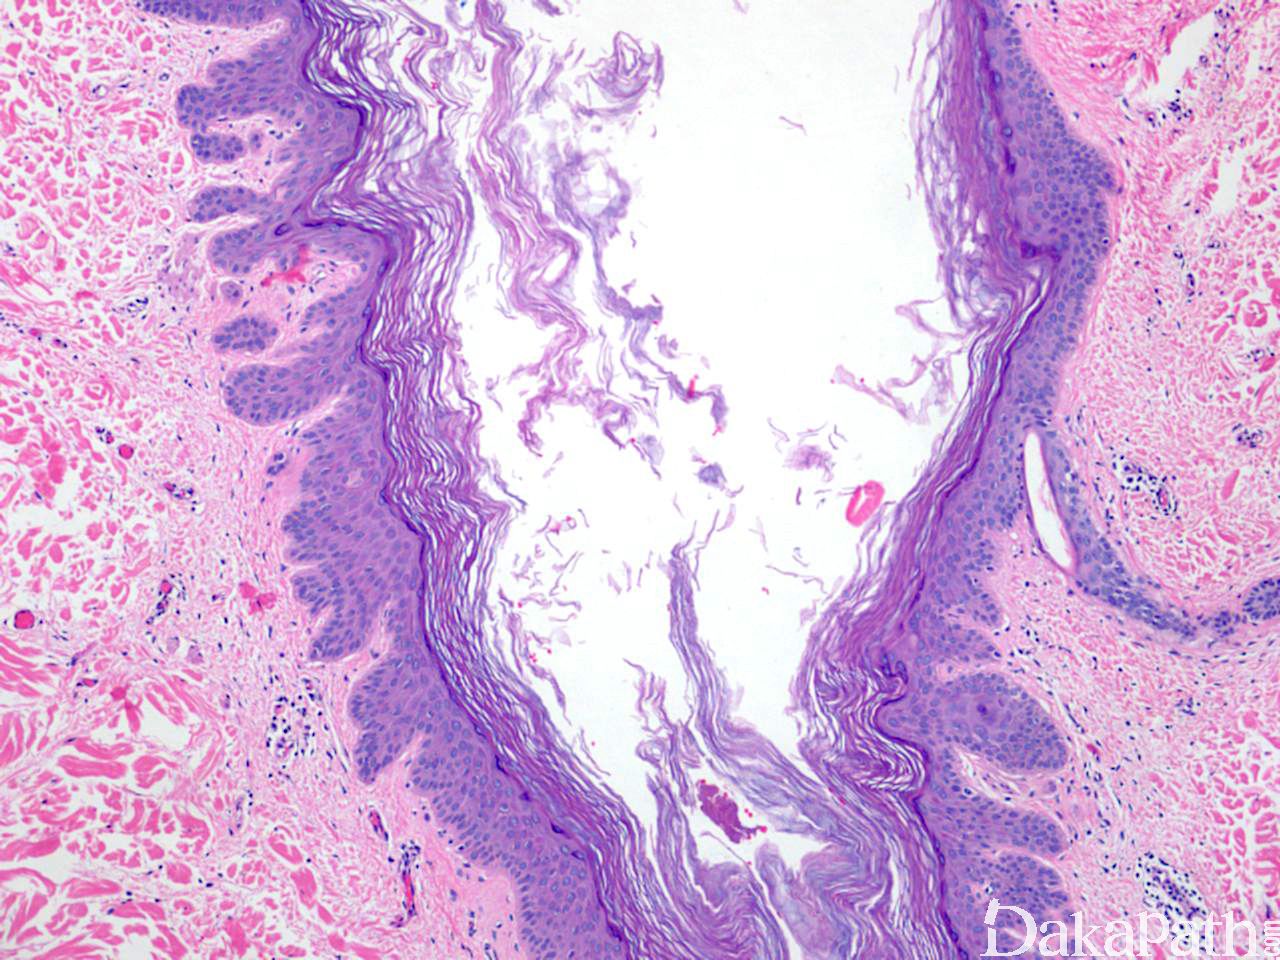

扩张毛孔

Dilated Pore

发病部位: 以面部为主

诊断要点:

1. 好发于中老年,男性多于女性,以面部为主;

2. 单发皮损,外观似巨大黑头粉刺的;

3. 毛囊漏斗部扩张,开口于表皮,内含角化物。